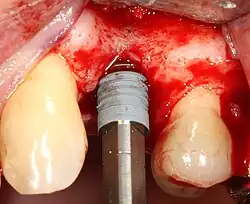

- Drilling at high speed: After reflecting the soft tissue, and using a surgical guide or stent as necessary, pilot holes are placed with precision drills at highly regulated speed to prevent burning or pressure necrosis of the bone.

- Drilling at low speed: The pilot hole is expanded by using progressively wider drills (typically between three and seven successive drilling steps, depending on implant width and length). Care is taken not to damage the osteoblast or bone cells by overheating. A cooling saline or water spray keeps the temperature low.

- Placement of the implant: The implant screw is placed and can be self-tapping;[50]: 100–102 otherwise, the prepared site is tapped with an implant analog. It is then screwed into place with a torque controlled wrench[54] at a precise torque so as not to overload the surrounding bone (overloaded bone can die, a condition called osteonecrosis, which may lead to failure of the implant to fully integrate or bond with the jawbone).